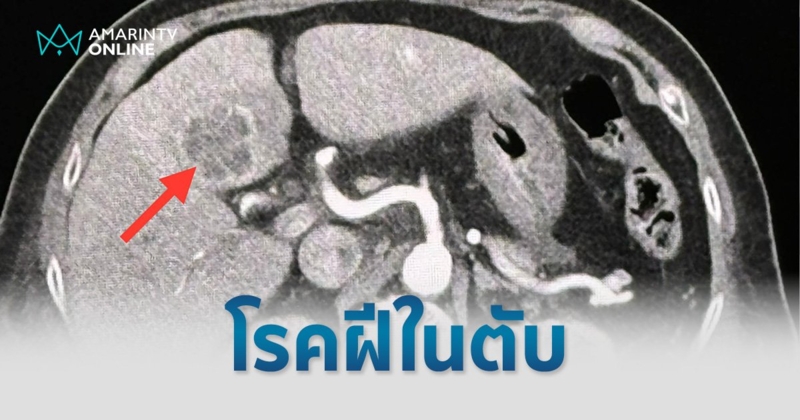

"ผู้ป่วยชายไทยอายุ 75 ปี เคยป่วยเป็นวัณโรคปอดเมื่ออายุ 25 ปี รักษาหายแล้ว ไปหาแพทย์ที่โรงพยาบาลใกล้บ้านเดือนเมษายน 2567 ด้วยอาการเบื่ออาหาร น้ำหนักลด ไม่มีไข้ ไม่ไอ ไม่มีเสมหะ เอกซเรย์ปอดผิดปกติ มีจุดและพังผืดที่ปอดข้างขวากลีบบน กลีบกลาง และปอดข้างซ้ายกลีบบน (ดูรูป)